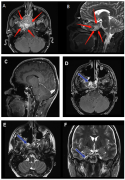

对于位于中线的CCJ肿瘤,较近内窥镜鼻内入路(EEA)的进展较大地提高了这个深部位置的切除率。巴黎Lariboisiere大学医院的核磁共振成像(MRI)初步检查显...